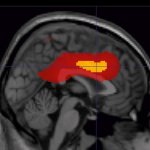

Implantate im MRT? Aber sicher!

Implantate und MRT – das klingt für viele noch immer nach No-Go. Dabei ist diese Gleichung längst überholt. Warum sich das Vorurteil trotzdem hartnäckig hält – sogar unter Fachleuten – und was sich dagegen tun lässt, diskutierten Experten auf dem Europäischen Radiologiekongress (ECR) in Wien.